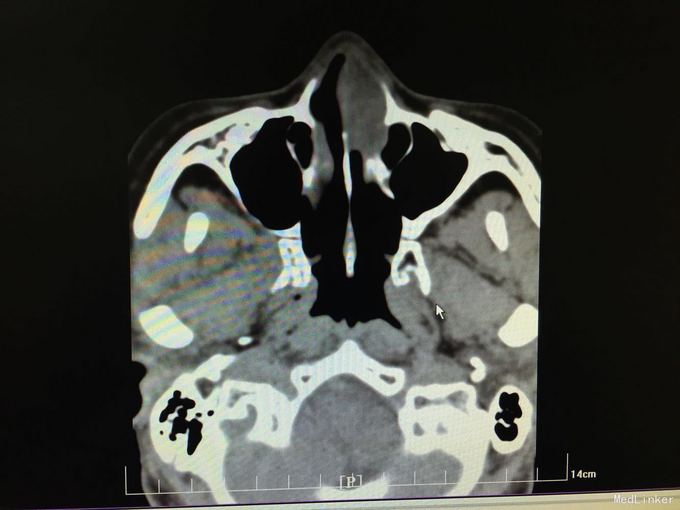

以“间断性左鼻腔出血5月,加重1月”为主诉入院。5月前劳累后出现左鼻腔出血,量中等,可自止,无明显鼻塞、流涕、鼻腔异味,自行口服药物后异味消失(具体药物不详),未正规治疗,1月来左侧鼻腔间断性出血,约3-5天1次,量少,偶浓涕、头晕,无明显鼻痒、喷嚏症状。

查体:双侧鼻腔黏膜充血,左侧总鼻道可见肿物,表面糜烂,质硬,触之易出血,左侧中鼻道窥不及,右侧鼻腔各鼻道未见明显新生物,无活动性出血,鼻中隔偏曲。 增强CT显示肿物内强化明显。

诊断:1.鼻腔血管瘤(左) 2.鼻出血(左) 3.结构性鼻炎 介入手术后3天行低温等离子左鼻腔肿瘤切除术